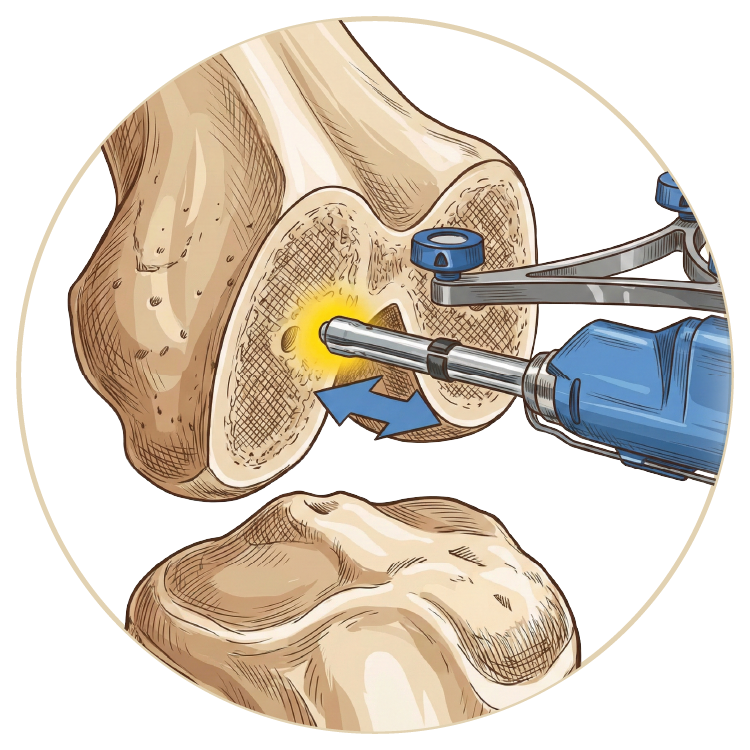

Artroskopi

Diz Artroskopisi

Kalça Artroskopisi

Omuz Artroskopisi

Dirsek Artroskopisi

Ayak Bileği Artroskopisi